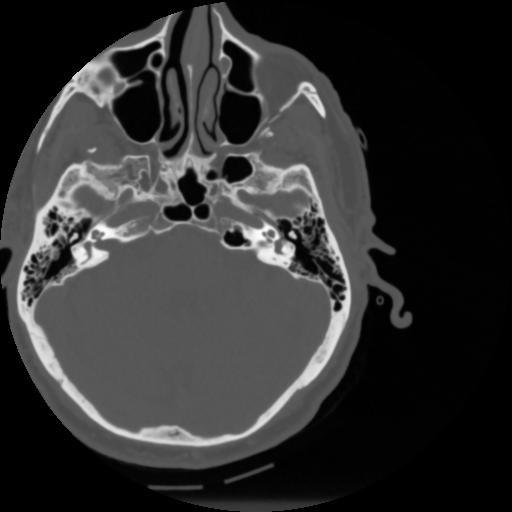

4 CEREBRO,,Vol,0.5,CEREBRO,,